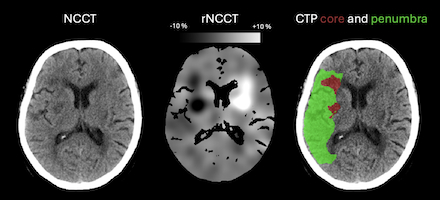

Abstract Body: Introduction and aims: Infarcted brain tissue on non-contrast computed tomography (NCCT) causes hypodensity resulting from vasogenic edema. It is unknown if hypoperfusion outside of the ischemic core may result in density changes on NCCT. This study aimed to evaluate the presence of hypodensity in the CT Perfusion (CTP) based penumbra.

Methods: We included ischemic stroke patients with anterior circulation large vessel occlusions transferred from a primary to a comprehensive stroke center for consideration of thrombectomy from the CRISP2 study. Patients underwent baseline NCCT and CT Perfusion (CTP) at the referring hospital and MRI at the comprehensive center. All images were coregistered to the NCCT. We created relative NCCT (rNCCT) maps on baseline imaging, which is an automated NCCT analysis that compares voxel density to the corresponding area in the contralateral hemisphere. Density alterations on rNCCT were represented as percentages, e.g. -1% represented 1% relative hypodensity compared to the contralateral region. We analyzed relative voxel hypodensity on rNCCT within the core (defined as relative cerebral blood flow <30%) and penumbra (defined as time-to-maximum (Tmax) > 6 seconds minus core lesion volume) (Figure 1). Furthermore, we evaluated the relationship between relative density changes and hypoperfusion severity within the penumbra. To ensure that our findings were restricted to the penumbra, we performed a sensitivity analysis using the diffusion-weighted imaging (DWI) lesion at the receiving hospital to define the ischemic core.

Results: We included 169 patients with a median penumbra volume of 78 ml (IQR 51-112) and core volume of 1.3 ml (IQR 0-13.3) (Table 1). The median relative voxel hypodensity in the penumbra was 1.8% (p<0.001) and 3.4% in the core (p<0.001). Relative hypodensity in the penumbra was greater with increasing hypoperfusion severity: median 1.5% in areas with Tmax delay between 6 to 8 seconds; median 1.9% in Tmax 8 to 10 seconds; and median 2.2% in Tmax> 10 seconds (p<0.001) (Figure 2). Using the DWI lesion as the core did not alter the results.